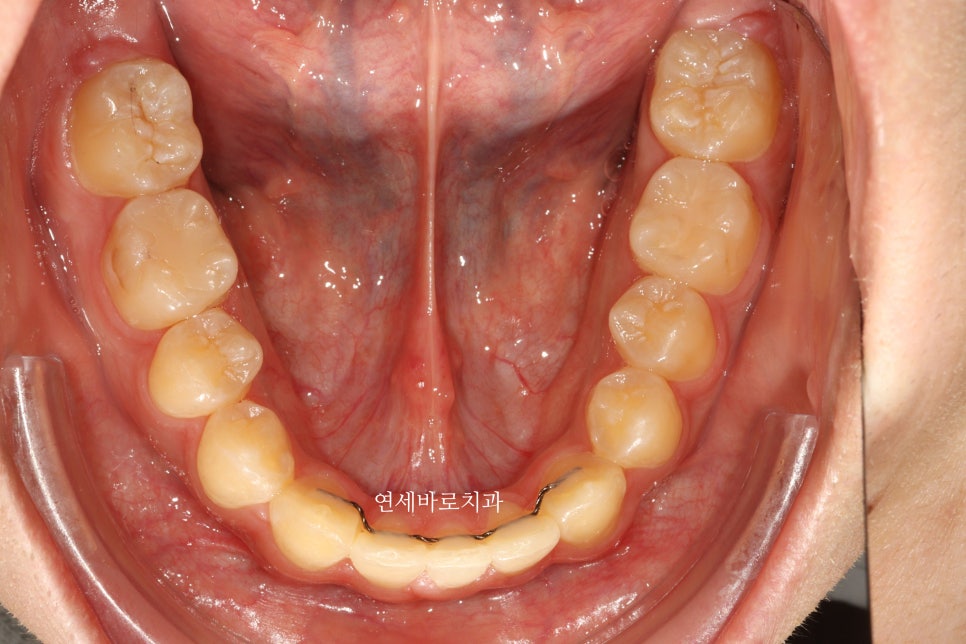

이때 아래 앞니를 하나 발치했습니다.

이유는 치아의 갯수를 맞추고, 중심선을 일치시키기 위함입니다.

필수는 아니었지만, 상담 후 결정하였습니다.

화살표 치아를 발치했고, 클리피씨를 이용해 치료를 진행했습니다.